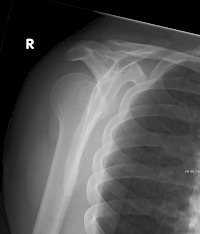

In Deutschland passieren jährlich etwa 13 600 Schulterluxationen. Der Anteil dorsaler Schulterluxationen beträgt dabei lediglich 1,7 bis 7 Prozent. Die hintere Luxation ist meist Folge indirekter Gewalteinwirkung, etwa bei generalisierten Muskelkrämpfen.

Die Diagnose der hinteren Schulterluxation lässt sich in der Regel durch Röntgenaufnahmen stellen.

Allerdings: Die Diagnose einer hinteren Schulterluxation ist besonders bei adipösen und muskulösen Patienten schwer zu stellen und auf dem Röntgenbild kann der Ungeübte leicht mal eine hintere Schulterluxation übersehen.

Bedient man sich jedoch visueller Hilfsmittel wie dem Glühbirnen- oder Eistüten-Zeichen auf den anterior-posterioren Aufnahmen, fällt es leichter.

So projiziert sich beim Glühbirnen-Zeichen das Tuberculum majus wegen der Verdrehung des Oberarmes in den Humeruskopf hinein, was an den Glühdraht einer Glühbirne erinnert.